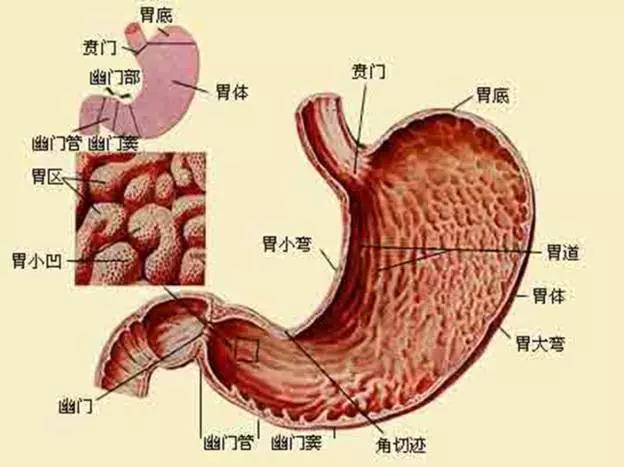

胃的解剖学特点:

胃通常分4部: 贲门部 胃底 胃体 幽门部

胃窦

?胃窦:胃窦指的是幽门与胃角切迹平面之间的部分